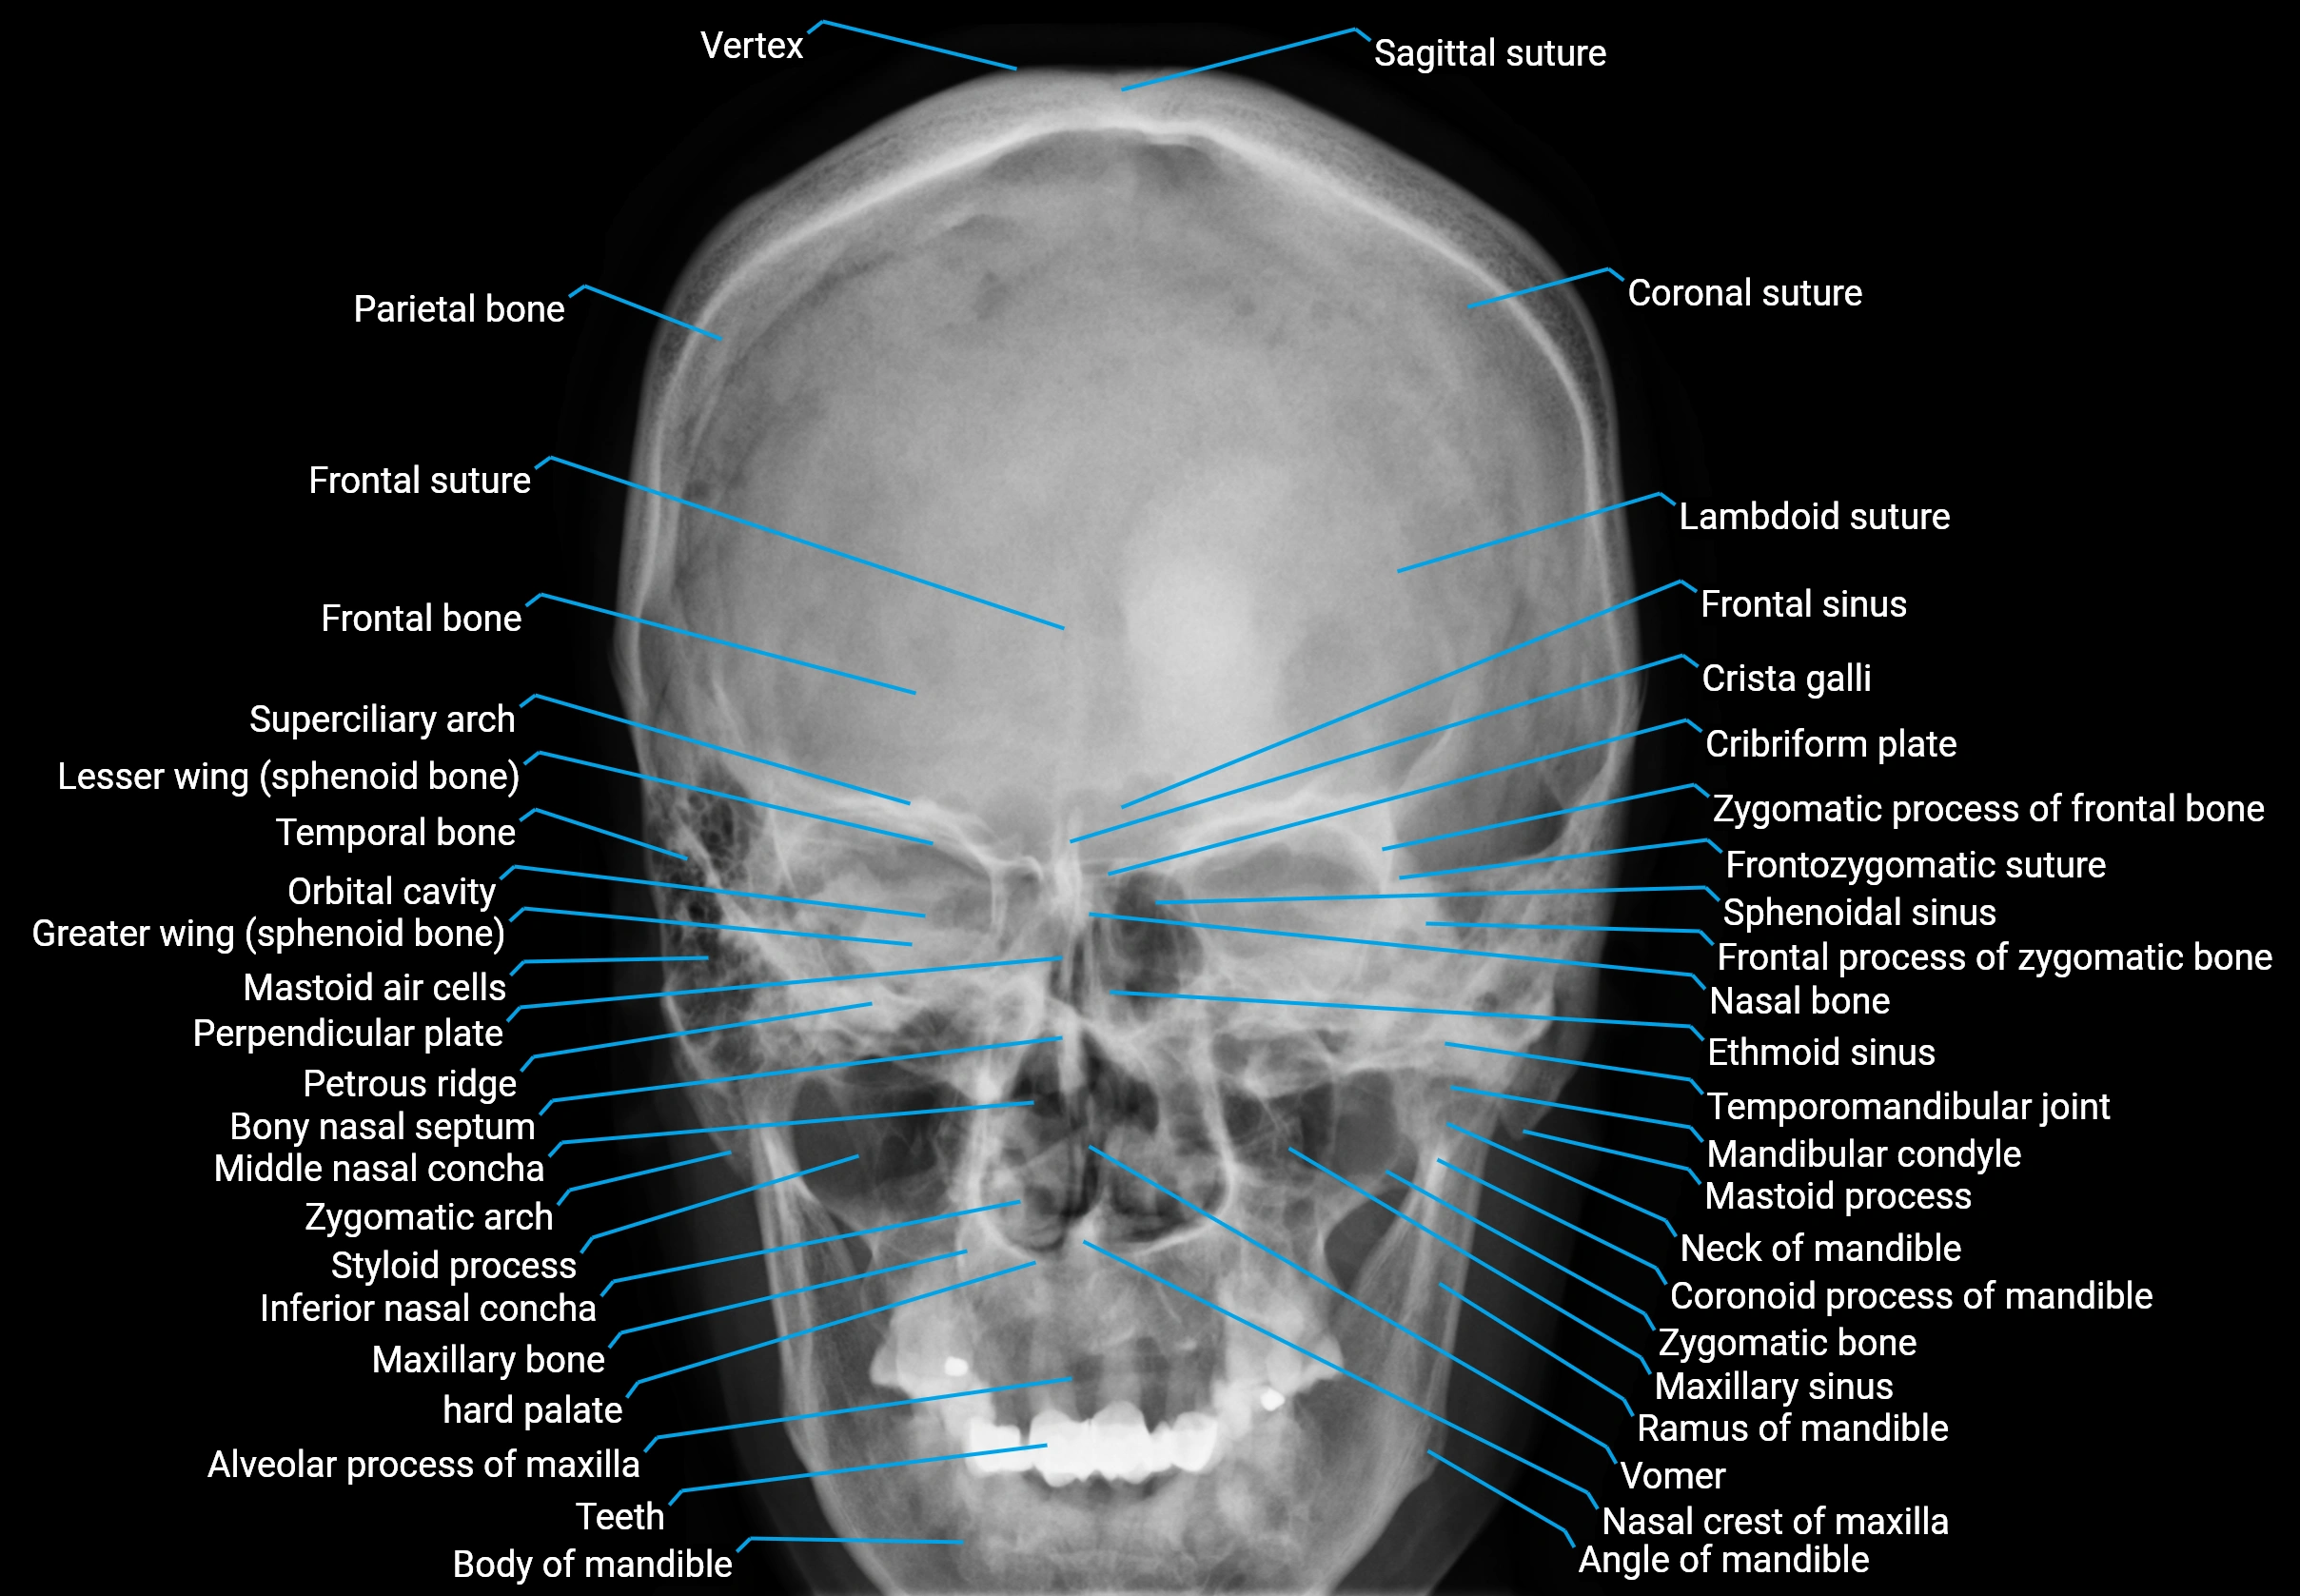

X-ray appearance

Dental and skull radiographs (periapical / panoramic / occlusal views):

• Alveolar arch: Curved radiopaque bony ridge

• Dental sockets: Radiolucent spaces surrounded by radiopaque lamina dura

• Alveolar crest: Thin radiopaque line between teeth

• Relationship to teeth: Clearly delineated tooth roots within alveoli

X-Ray image

image